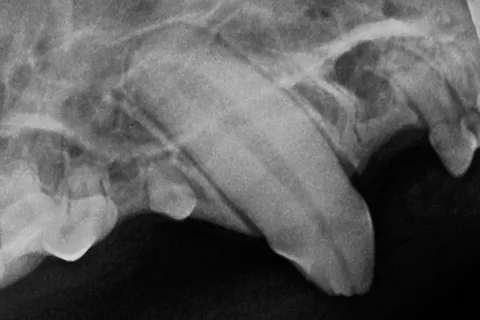

Fig. 1: Fractured upper canine tooth in a cat.When a cat breaks a tooth and exposes the pulp, bacteria and oral debris enter the tooth. As a result, a painful inflammation of the pulp (pulpitis) develops, eventually causing the nerves and blood vessels to die. The bacteria then move out of the bottom of the root (the root apex) and infect the bone surrounding the root (called apical periodontitis).

Both pulpitis and apical periodontitis are very painful. Once a tooth is broken with the pulp exposed, there are only two choices for treatment: root canal therapy or extraction.